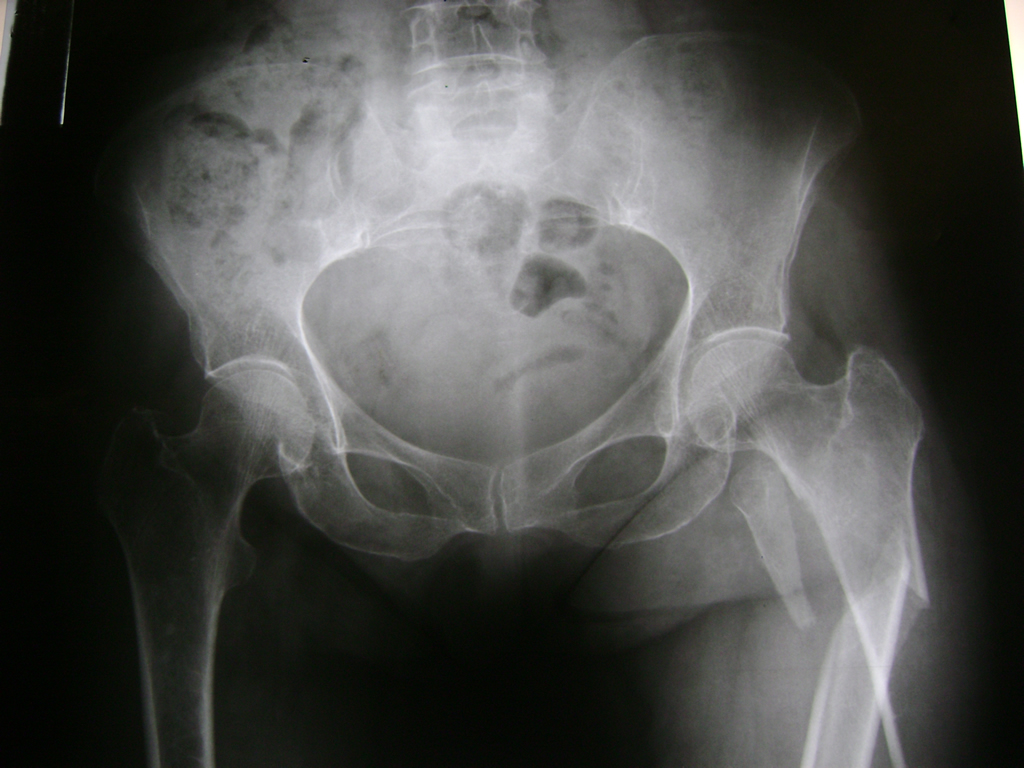

La cirugía de fractura de cadera se realiza para reparar una ruptura en la parte superior del hueso del muslo. Este hueso se denomina fémur.

Es parte de la articulación coxofemoral. Si una fractura de cadera no recibe tratamiento, es posible que deba permanecer en una silla o en la cama.

Esto puede llevar a otros problemas de salud potencialmente mortales, sobre todo si usted es una persona mayor.